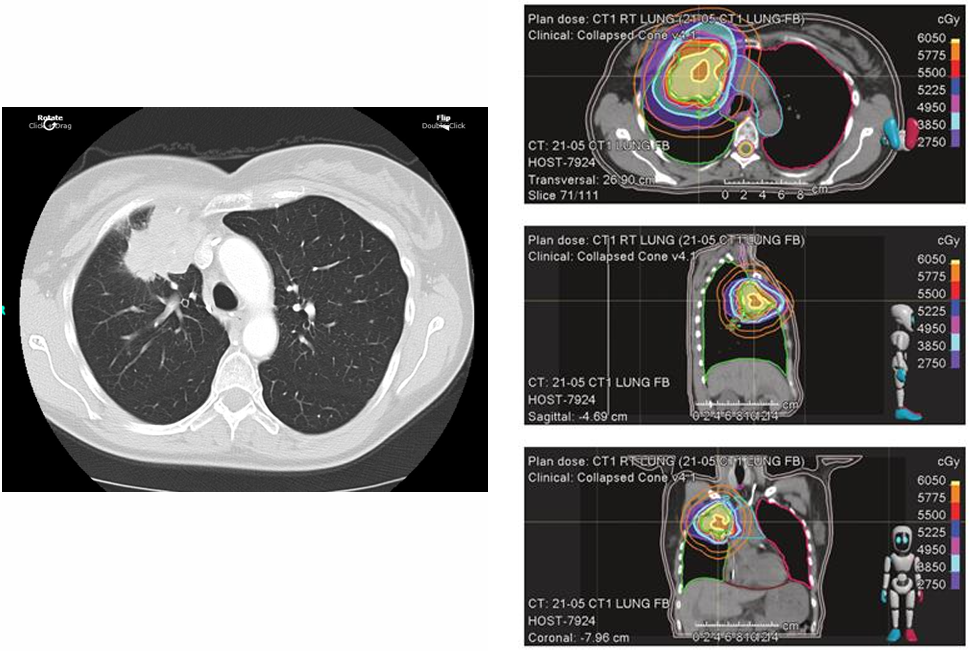

胸部CT显示,右肺上叶巨大肿块(6.5cm),伴双侧多发肺结节及纵隔淋巴结肿大。脑MRI未见转移。

临床诊断:肺腺癌,cT3N2M1b(IVB期)。

分子特征:KRAS G12C突变,伴随STAK11突变、ATM突变、PTEN缺失(FISH阳性);PD-L1表达阳性(22C3检测为表达),微卫星稳定(MSS),肿瘤突变负荷(TMB)低;无EGFR、ALK、ROS1、RET、BRAF等基因异常。

b332ee7c-8b1d-48cf-825b-0421f00386bb.png

局部治疗:接受SBRT治疗,55Gy/10次。